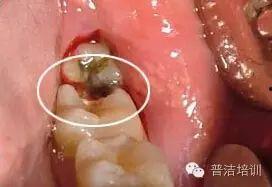

成人牙齿有虫子视频,警惕口腔健康隐患

最近在网上看到一个视频,简直让人毛骨悚然!说的是成人牙齿里竟然有虫子,这可真是让人意想不到的事情。今天,我们就来聊聊这个话题,看看这背后到底隐藏着什么秘密。牙齿里的虫子,真的存在吗?首先,我们要明确一点,牙齿里的虫子...